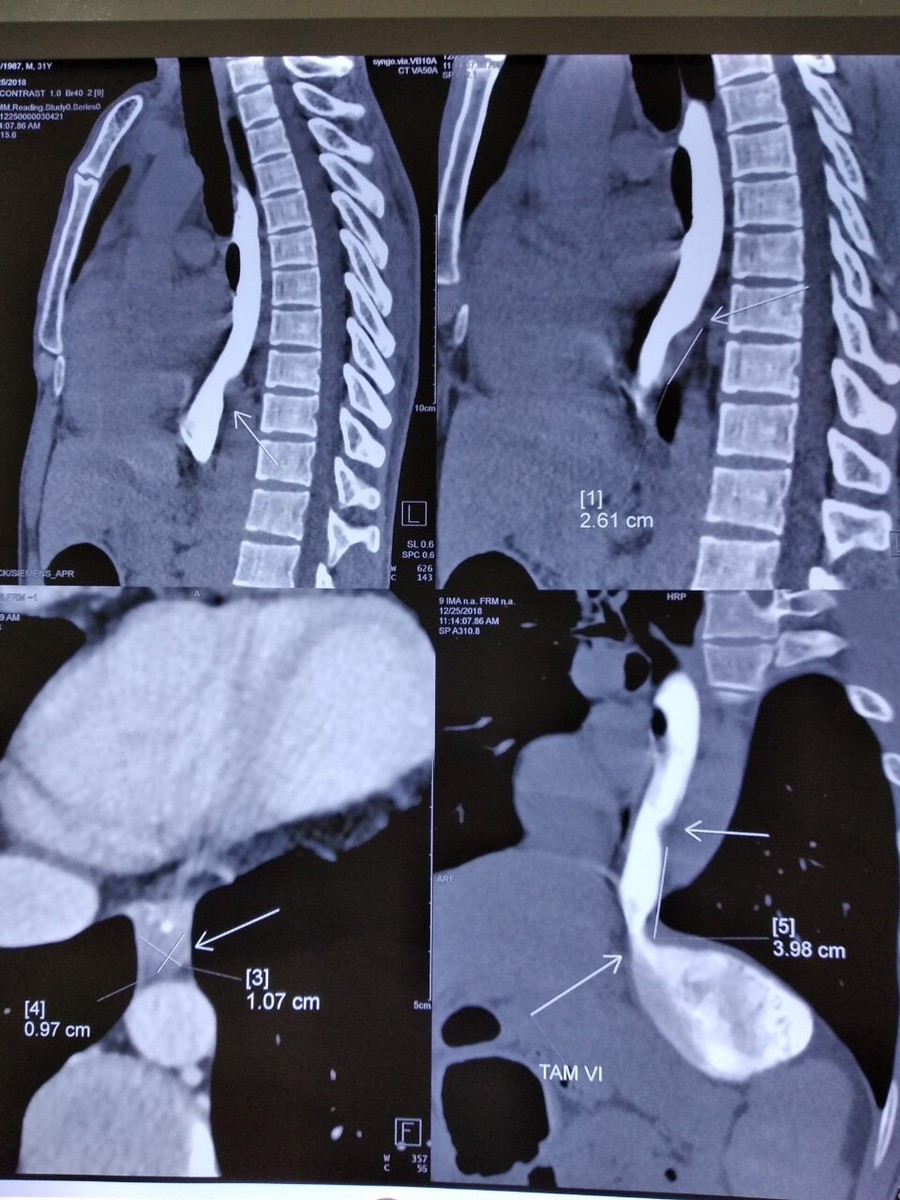

Sau khi chụp chiếu, làm các chỉ định, xét nghiệm cần thiết và nội soi dạ dày, thực quản anh H. được chẩn đoán có khối u xơ dưới niêm mạc thực quản.

Phim chụp khối u

Nhận thấy tổn thương là u xơ, tuy nhiên anh H. đã đau khoảng 2 tuần, các triệu chứng không thuyên giảm, bác sĩ bệnh viện K đánh giá chưa loại trừ tổn thương có dị vật thực quản.

Bằng kinh nghiệm lâu năm, các bác sĩ thực hiện phẫu tích tỉ mỉ đã lấy trọn vẹn tổn thương viêm xơ ở thực quản kích thước 3x4cm trong đó có dị vật xương cá.